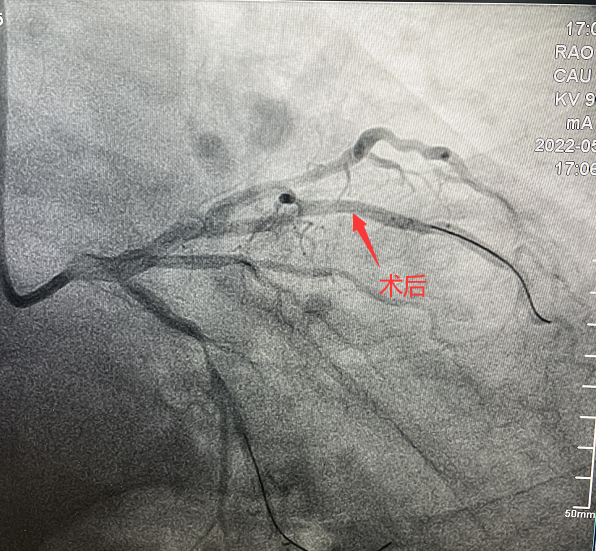

患者,51歲,男性,入院診斷為:冠心病、不穩(wěn)定型心絞痛。冠狀動(dòng)脈造影顯示對(duì)角支90%狹窄病變。對(duì)于該類患者,通過(guò)介入治療(PCI)方式早期干預(yù)相關(guān)血管可明顯減輕患者癥狀,減少死亡率、并發(fā)癥,改善患者的預(yù)后。在醫(yī)生與患者及家屬溝通時(shí),患者家屬提到,他們了解得知臨床有一種新型的可吸收支架,置入體內(nèi)后能完全被降解和吸收,患者及家屬希望能用這種新型的支架進(jìn)行手術(shù)治療。由于生物可吸收支架有著嚴(yán)格的適應(yīng)癥,因此經(jīng)過(guò)嚴(yán)格評(píng)估,最終對(duì)患者進(jìn)行了Xinsorb生物可吸收支架(BRS)置入術(shù)。支架植入術(shù)后,經(jīng)IVUS檢查,支架貼壁良好,結(jié)果完美,手術(shù)順利結(jié)束。

手術(shù)造影圖